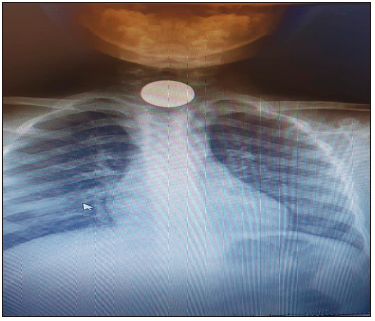

El manual de Prevención de Accidentes de la Sociedad Argentina de Pediatría del 2005 menciona la ingestión de cáusticos y cuerpos extraños como una problemática de salud pública. Aunque solo el 10% de las pilas ingeridas generan síntomas, su ingestión entraña riesgo de perforación esofágica y se considera una urgencia vital debido a que en su composición se encuentra hidróxido de potasio o de sodio, sustancias que provocan una rápida necrosis de los tejidos. Aunque los juguetes de metal o plástico son menos comunes actualmente, su incidencia se ha reducido gracias a las normativas de seguridad en su fabricación.

Por esta problemática, es crucial realizar radiografías tan pronto como se sospeche la ingestión de un cuerpo extraño para determinar su ubicación y, especialmente, para identificar la presencia de una pila, dado que estas suelen tener una ranura circunferencial característica (Foto 3). Las monedas siguen siendo el cuerpo extraño más comúnmente encontrado (Foto 4), lo cual no ha cambiado, a pesar de la disminución de su uso en transacciones comerciales, debido a la economía actual.

Foto 3. Pila botón en región cricofaríngea

Foto 4. Moneda en región cricofaríngea